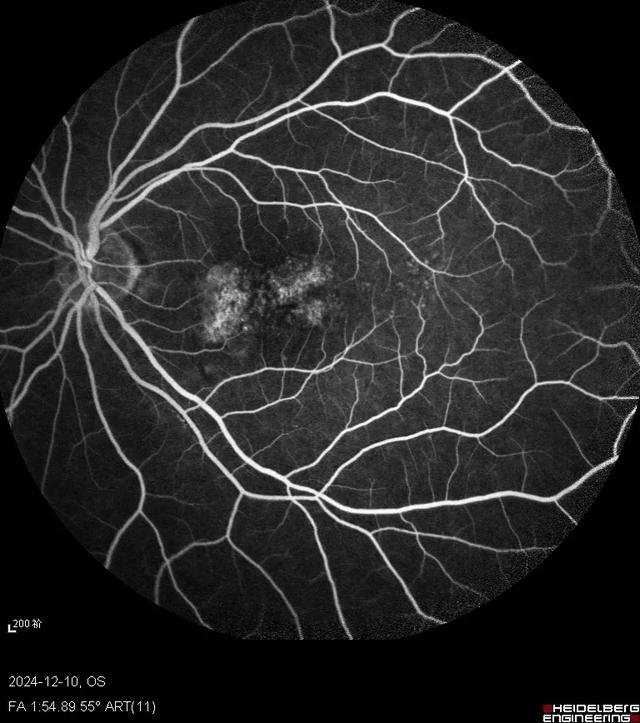

马上对此患者进行了抽血检查来判断是否存在梅毒感染,另外还安排了眼底荧光素血管造影(FFA)和吲哚菁绿(ICG)造影检查。因为我们知道梅毒是“模仿大师”,可以引起视神经炎、视网膜血管炎、脉络膜炎等多种眼底改变。很快造影结果就出来了,右眼FFA黄斑早期高荧光,晚期高荧光衰减;而ICG则早期低荧光,晚期高荧光;左眼FFA黄斑渗漏较右眼明显,ICG晚期也是表现为高荧光。双眼自发荧光类似,表现为中央低荧光,围绕一圈周围高荧光。果不其然,符合这时候梅毒性后极部鳞状脉络膜视网膜炎的临床表现。

FFA右眼

FFA左眼

关于梅毒性后极部鳞状脉络膜视网膜炎,《中华眼科杂志》有一篇彭晓燕教授的文章,总结的很好,我引用一下1。彭老师的这组患者共10人,其中8人为双眼发病。视力介于指数~0.8,中位数0.3。仅1例患者出现前房炎症反应。眼底病变均集中在以黄斑为中心的后极部。6只眼表现为鳞样病灶,4只眼表现为弥漫黄白色病灶,其余是混合型。OCT提示主要累及外层视网膜,显著特征是椭圆体层部分或全部消失,RPE结节,玻璃体内细胞。自发荧光表现为斑片状或弥漫高荧光。FFA静脉后期开始轻度高荧光,晚期渗漏。ICGA中晚期低荧光,夹杂针尖状高荧光点。在文献的引导下,我重新回顾了一下OCT,当我把扫描线拉到黄斑区外时,确实发现了很多玻璃体细胞,所以看OCT时还需要更仔细一些。

梅毒性后极部鳞状脉络膜视网膜炎的临床特征包括青壮年、急性双眼起病、视力下降显著而眼部体征较轻。OCT上黄斑区椭圆体带不同程度损伤伴有RPE结节和玻璃体细胞。自发荧光、FFA、ICG、眼底彩照表现为后极部累及黄斑区鳞片状或弥漫性病灶。在临床分析中,要抓住点点滴滴的蛛丝马迹,往往一些容易被忽略的小问题最后会成为“破案”的钥匙,借此病例,与眼科同道们共勉!